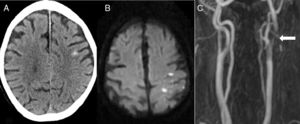

La segunda causa más frecuente fue el ictus isquémico (n=5): 2 ictus cardioembólicos, un infarto aterotrombótico, un ictus secundario a obstrucción carotidea y una trombosis de un stent carotideo (fig. 2).

Paciente de 82 años que, 6 días después de colocar un stent carotideo izquierdo, presenta pérdida de fuerza y sensibilidad en brazo derecho de inicio brusco. En el TAC cerebral (A) se aprecia una HSAc en la convexidad del lado izquierdo. La RM en secuencia de difusión (B) identifica un infarto agudo adyacente al sangrado. La angio-RM (C) muestra una trombosis del stent (flecha).